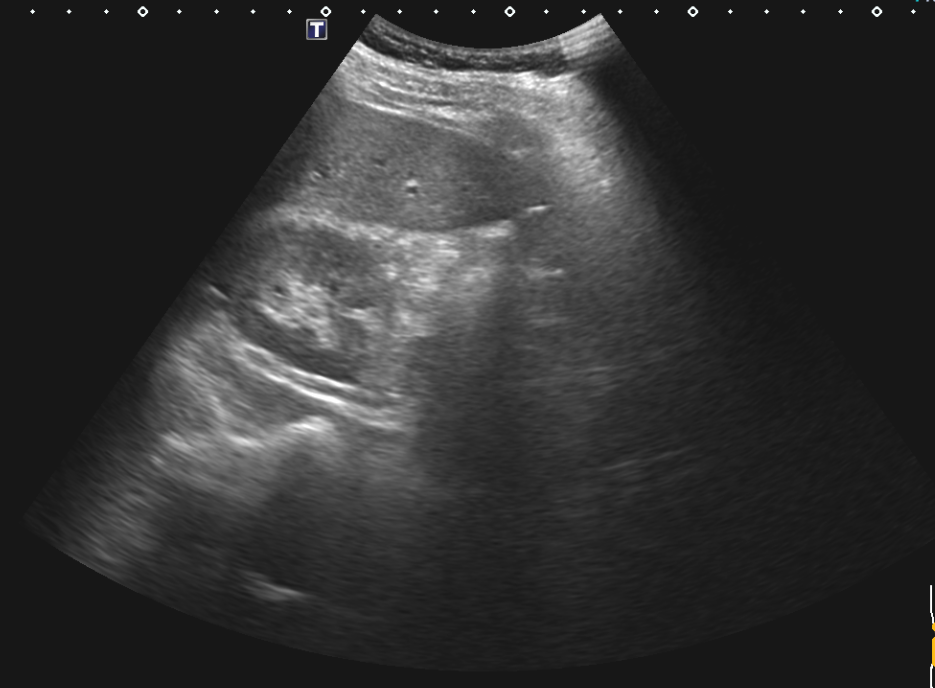

복부초음파 검사했는데요 초음파상 오른쪽신장 부근 사진인데 신장물혹이 보이나요?

혹시 복부초음파 오른쪽 신장부근 사진몇장올리는데.. 혹시 물혹이 보이시나요?

그리고 마지막사진 오른쪽 옆구리 맨윗부분 겨드랑이쪽 검사사진 중간에 검은점 저것은 무엇인가요.?

• 3번 째 사진

복부초음파 사진 여러 장 올린 것에 신장낭종은 잘 보이지 않는 것 같습니다

그리고 "오른쪽 옆구리 맨윗부분 겨드랑이쪽 검사사진 중간에 검은점" 는 어느 부분을 가리키는지

알 수가 없어서 드릴 말씀이 없네요